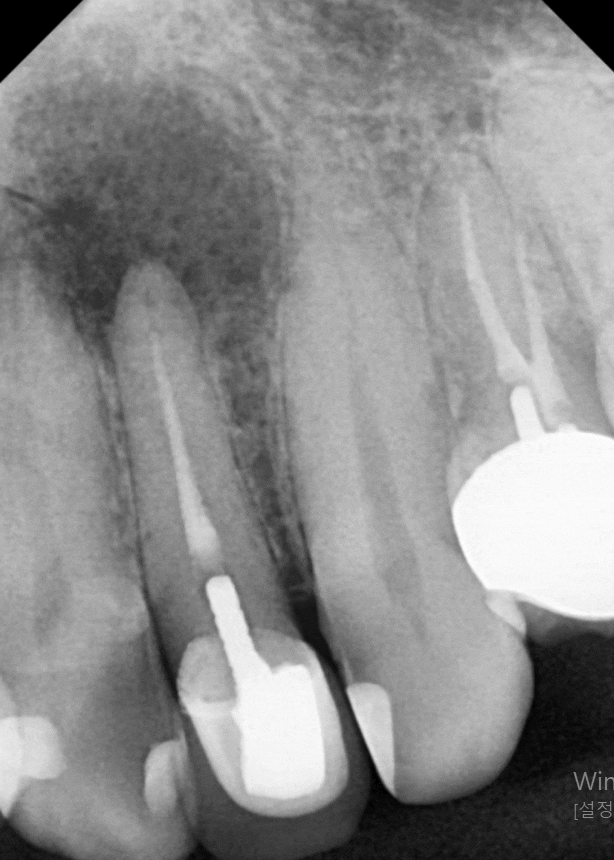

열 번의 소독이 끝난 후

다시 사진을 찍어보았는데요~

까맣게 비어있던 공간이 어떻게 변했을까요?

231129 (전) 240215 (후)

놀랍게도 구멍이 뻥 뚫린 것처럼 보였던

염증 부위가

이제는 거의 회복되어 뼈가 단단하게

차오른 것을 확인할 수 있었습니다.